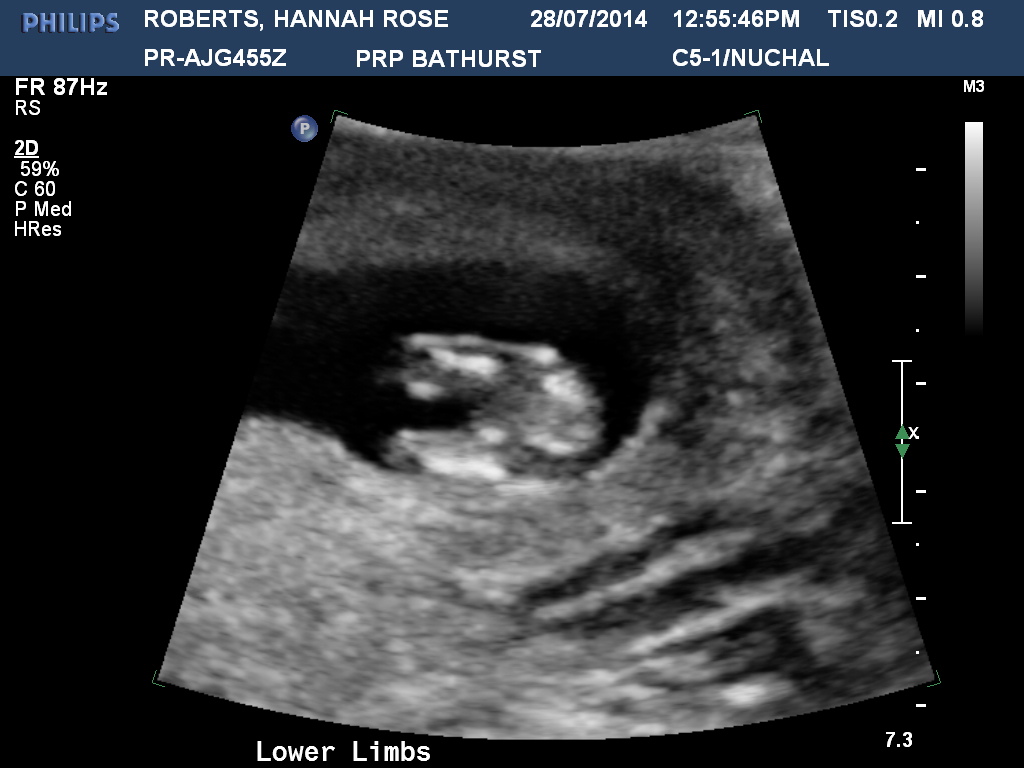

I have two beautiful little boys, and I am expecting my third child. I have a "gut" feeling this little one is a girl but it may just be wishful thinking! I had my 12 week scan yesterday and got a good potty shot, can you all have a look and tell me your thoughts on this?! Unfortunately I didn't get a potty shot for my two boys so I can't compare. Thank you!!:ttcgirl:Attachment 20049